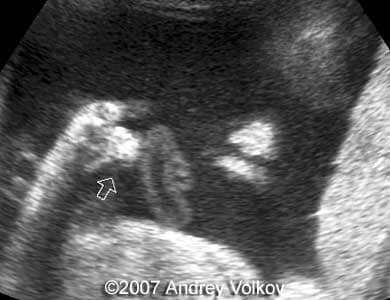

A 26-year old G1P0 from a nonconsanguineous couple (husband 35 years old), with noncontributive history, presented to our unit at 30 weeks of pregnancy. Our ultrasound examination revealed following findings:

• Cloverleaf shaped skull;

• Lobar holoprosencephaly;

Images 1, 2: 30 weeks of pregnancy; Image 1 shows cloverleaf shaped fetal skull. Image 2 shows transverse scan through the fetal skull with lobar holoprosencephaly.